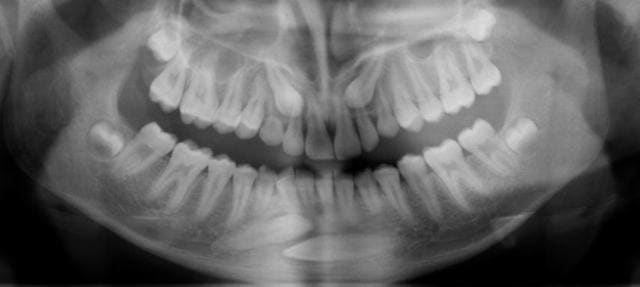

14 ans. C'est moi qui m'y colle mi-mai (dégagement chirurgical des couronnes et traction orthodontique).

Canines 14 ans a  qrvcnb - Eugenol

Canines 14 ans b  emt7bb - Eugenol

Le haut, c'est banal.

Par contre pour le bas, c'est une autre histoire... Je ne vois pas d'autre solution que des ancrages osseux latéraux pour y arriver sans télescoper les racines des incisives. Haut les coeurs ! On y arrivera !

En pièces jointes, les radios de contrôle faites à 11h45. Je n’ai pas encore eu le temps de traiter les photos.

4 canines otp da6shp - Eugenol

4 canines tele pjw3hq - Eugenol

Un système que je développe moi-même depuis quelques années et qui a des possibilités d’évolution qui semblent infinies (Rev Orthop Dento Faciale 2006;40:63-90). Ici, j’ai utilisé deux vis de chirurgie maxillo-faciale en tandem sous muqueuses. Y est accroché un fil en TMA .018 qui émerge en latéral le long du vestibule et vient tracter, comme une « canne à pêche » la ligature qui est collée directement aux couronnes des canines incluses.

En haut, système plus banal (si j’ose dire).

Oui, au cabinet sous anesthésie locale. D’abord le haut, puis le bas.

Difficile à dire, cela m’étonnerait quand même que cela puisse être inférieur à 18 mois compte tenu de la position de la 33. Dès que les incisives inférieures seront dégagées, j’attaquerai le traitement orthodontique proprement dit.